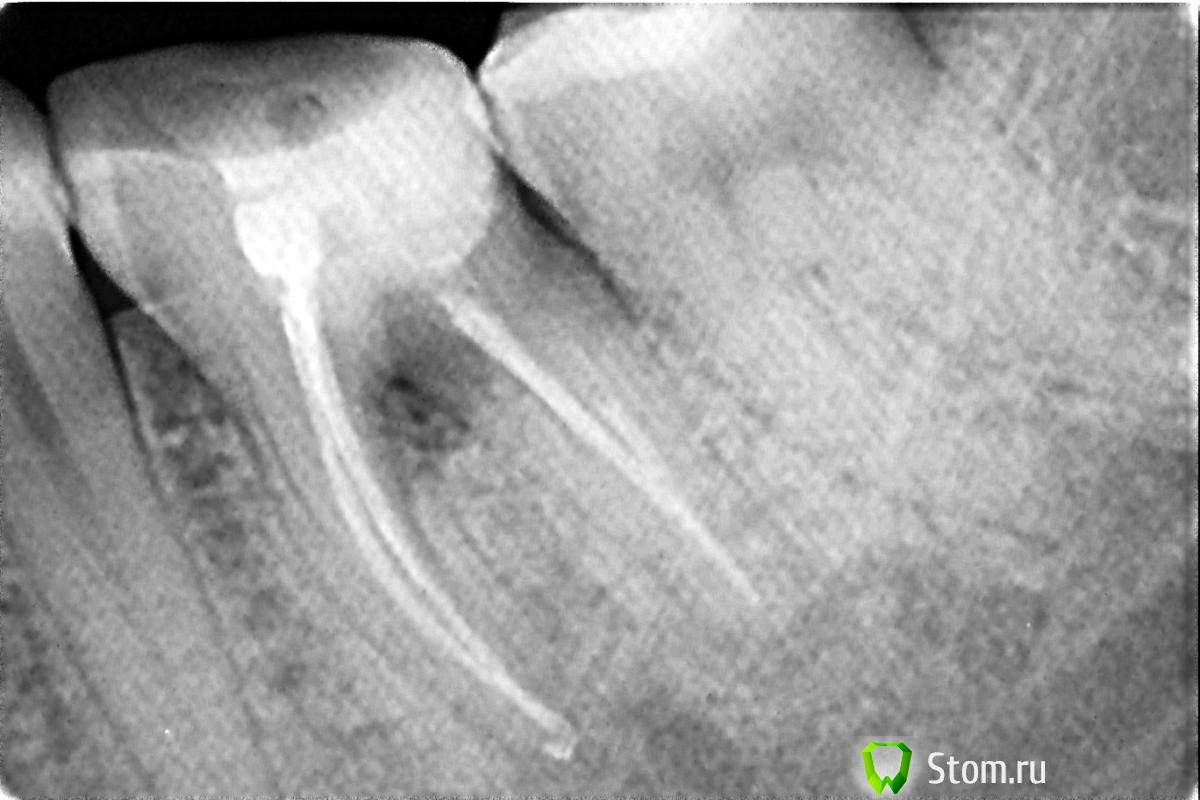

pho Опубликовано 2 апреля, 2012 Поделиться Опубликовано 2 апреля, 2012 (изменено) Добрый день! Мне 35 лет. Два года назад заболел зуб. В течении месяца ныло, под конец уже с сильной болью обратилась к врачу. Вскрыли пломбу, под пломбой оказался кариес. Удалили нервы, запломбировали каналы( а их оказалось 4 шт). Лечение стоило аж 8000руб. Через 2 месяца обнаружила свищ на десне этого зуба. Ничего не беспокоило. Сделала снимок(прилагается) . Затемнение между корней. В клинике где делали рекомендовали удалить . В других -наблюдать. Вопрос почему это случилось? Год спустя снимок показал без изменений, Недавно снова сделала снимок- тоже без изменени, свищ закрылся. Но сейчас уже 3 день как побаливает при нажатии. Что делать? Возможно ли в моем случае сделать коронко-радикулярную сепарацию, т.е разделить зуб на две части и провести соответствующую терапию? Изменено 2 апреля, 2012 пользователем pho Ссылка на комментарий

Magdalena Опубликовано 2 апреля, 2012 Поделиться Опубликовано 2 апреля, 2012 (изменено) Добрый день. По снимку складывается впечатление, что есть перфорация дна полости зуба, которую сделали во время лечения, в норме ее быть не должно. Возможно также в зубе есть трещина. Я бы больше порекомендовала удалить зуб, хотя как вариант, можно снять пломбу, оценить ткани на дне полости зуба и попытаться закрыть перфорацию (если она есть и если нет трещины), такое лечение будет без всяких гарантий. Но точно не заниматься никакими сепарациями - в итоге удалите и зуб и коронку, которой им закроют. Если хотите надежный результат - то это удаление и последующая установка имплантата в области удаленного зуба. Изменено 2 апреля, 2012 пользователем Magdalena Ссылка на комментарий

Afffinity Опубликовано 2 апреля, 2012 Поделиться Опубликовано 2 апреля, 2012 Это затемнение случилось из-за вины врача?Если перфорация то да. Но не на 100%. Больше похоже на трещину. Судя по размеру пломбы и проведенному лечению зуб нужно было покрывать коронкой. Тогда, возможно, этого бы не случилось. Опять же, все надо разбирать на месте. Обратитесь к доку, который делал этот зуб Ссылка на комментарий